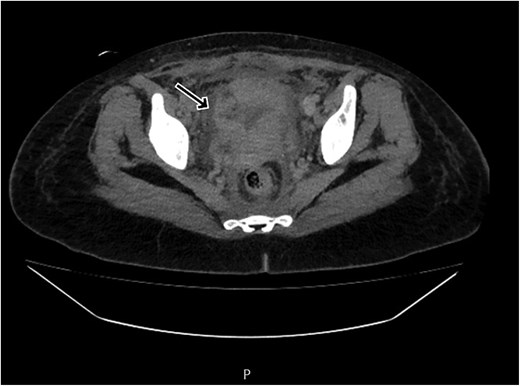

By postpartum day five, the patient exhibited persistent fever and worsening clinical status, unresponsive to broad-spectrum antibiotics. A contrast-enhanced computed tomography (CT) scan was performed, revealing a ruptured uterine scar with omental herniation and a large intra-abdominal abscess (Figs 1 and 2).

CT scan shows a linear small defect in the anterior wall of uterine fundus with small collection (2 × 1 cm).